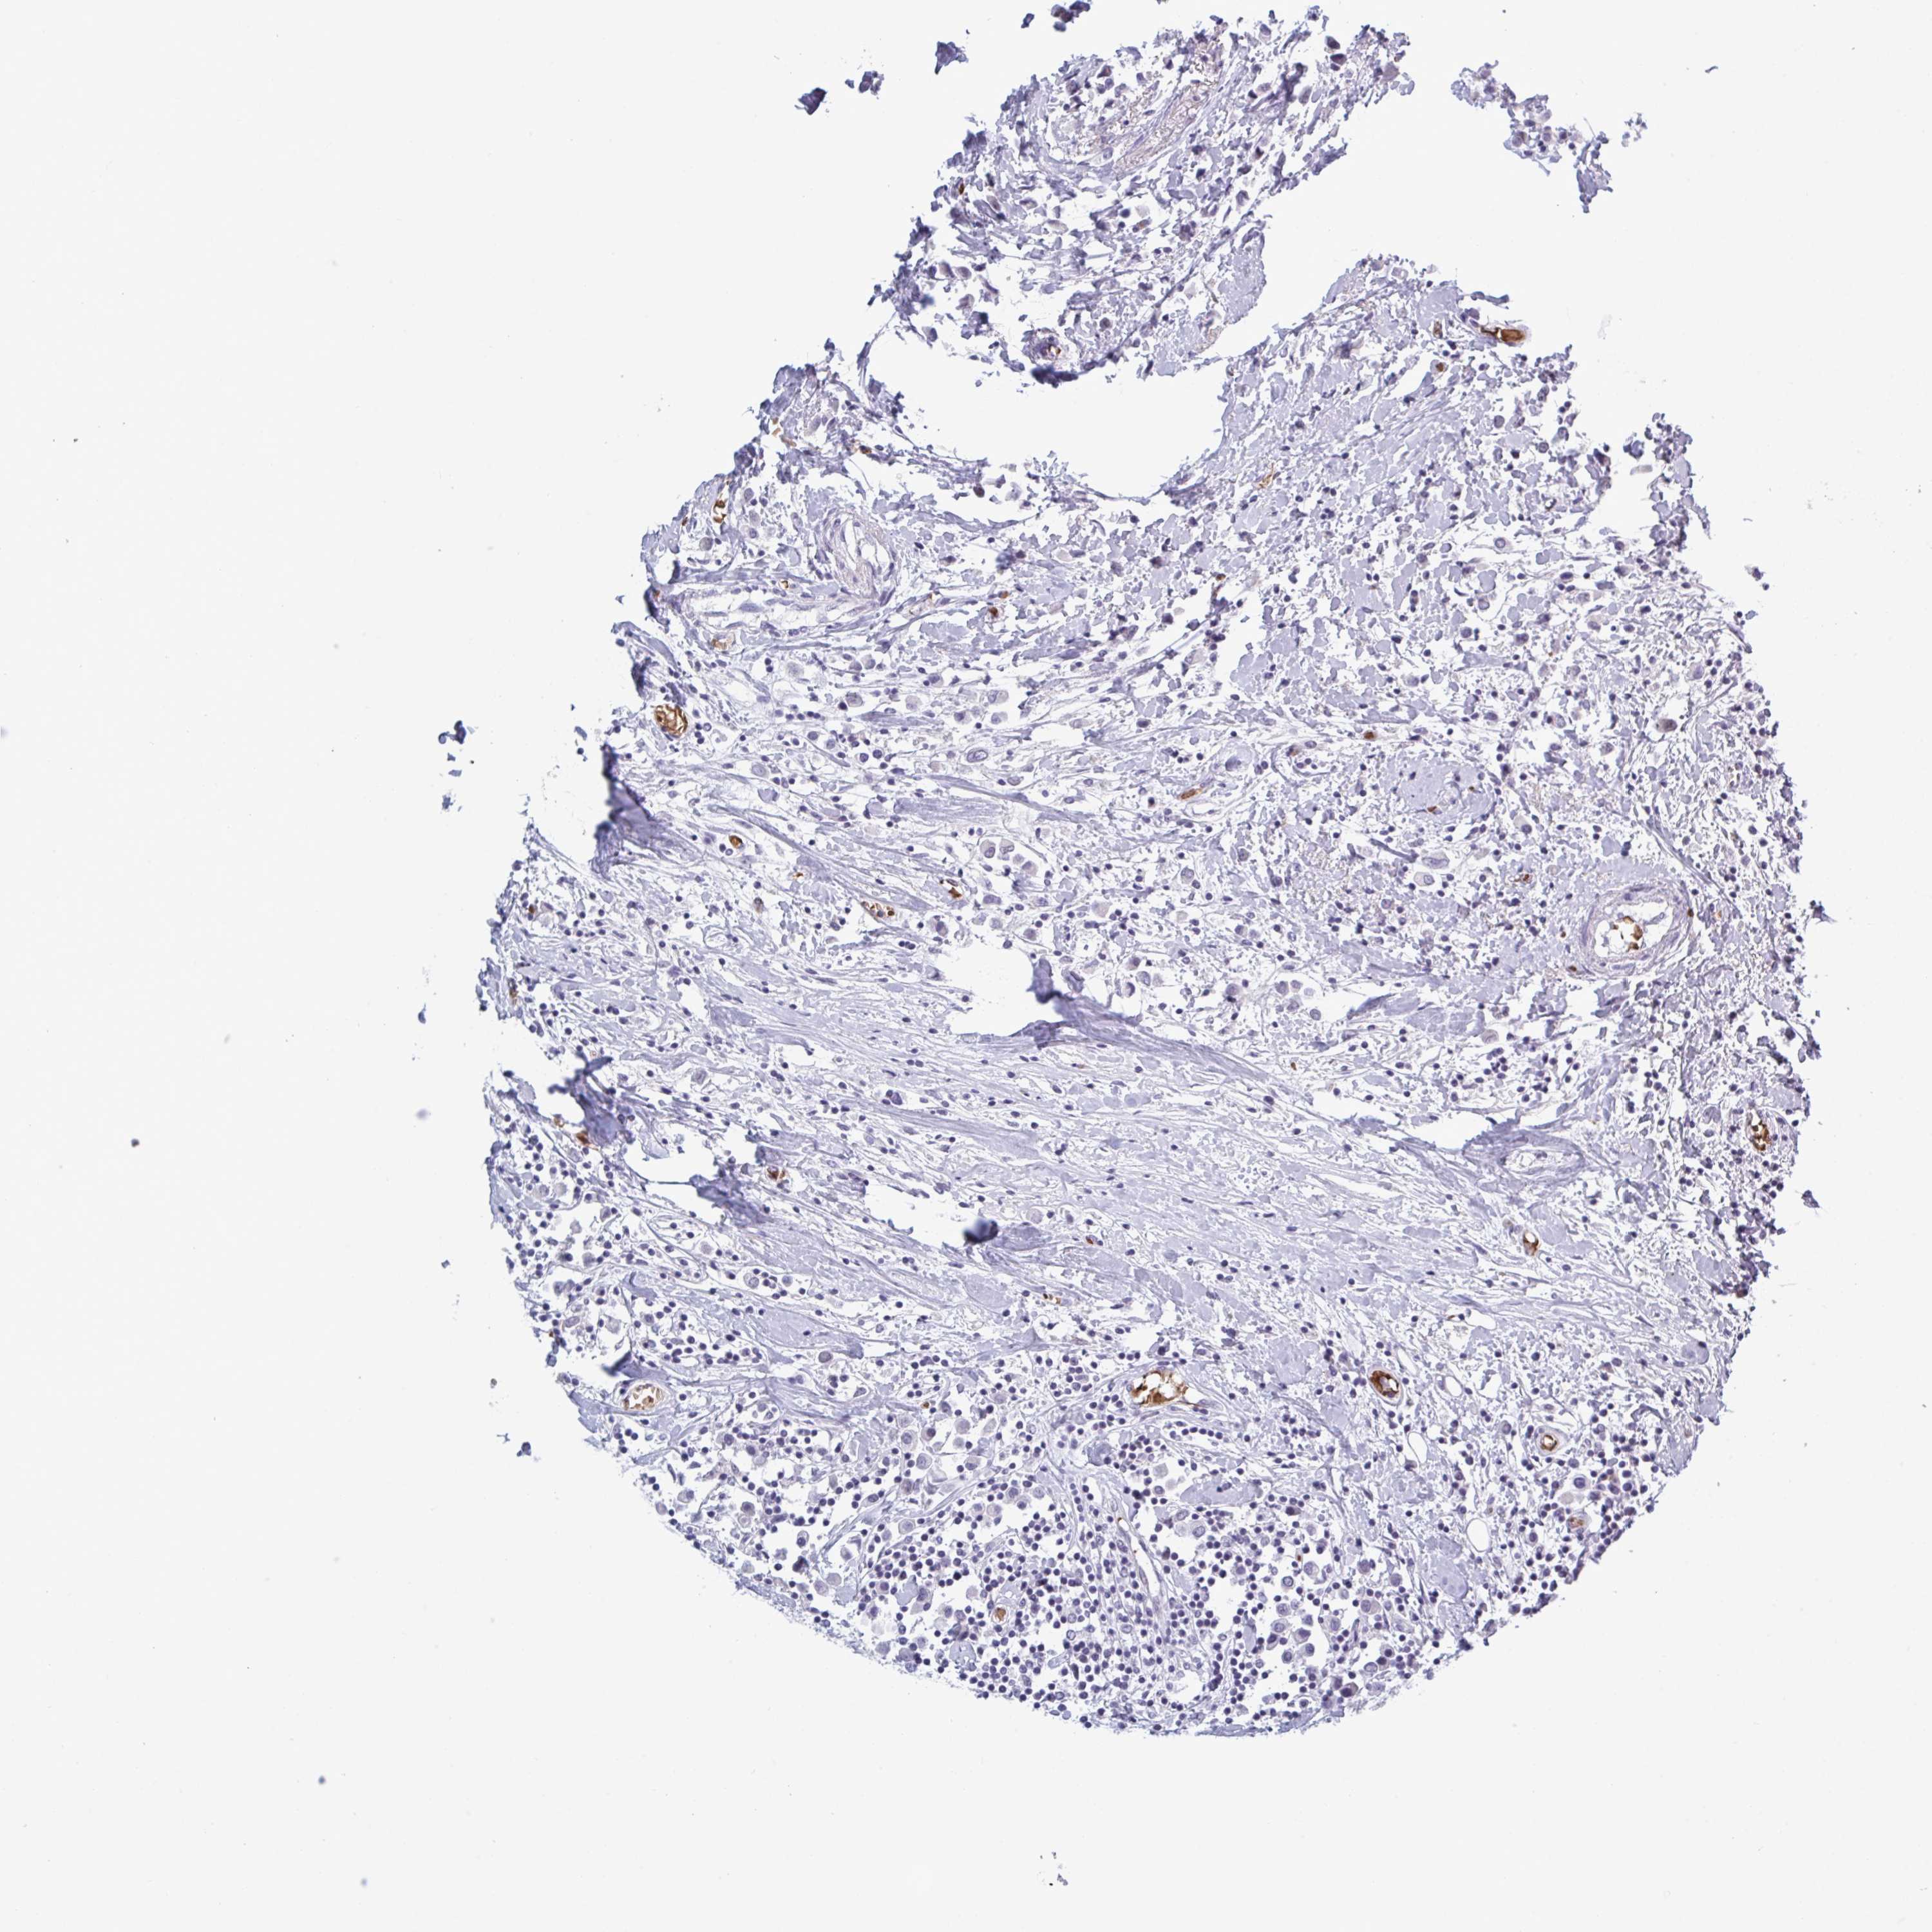

CANCER BREAST CANCER Show tissue menu

BRCA TCGA BRCA VALIDATION PROTEIN EXPRESSION